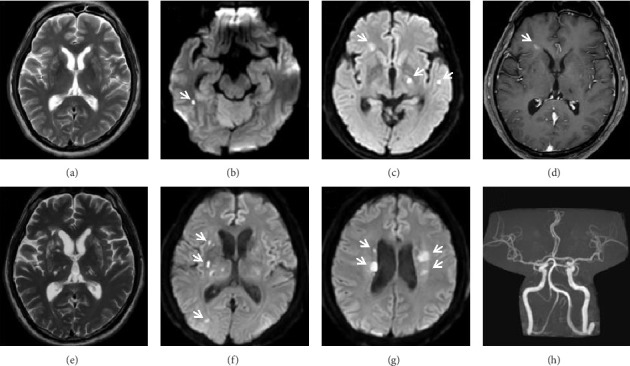

边缘带淋巴瘤(MZL)是一种惰性淋巴瘤,很少累及中枢神经系统(CNS)。边缘性B细胞淋巴瘤(CBL-MZ)是一种恶性前病变,指的是外周血中存在克隆B细胞,但没有器官肿大、淋巴结病变或其他已建立淋巴瘤的特征,可能罕见地进展为MZL,因此除了积极监测外不需要治疗。一名54岁男性,先前诊断为CBL-MZ,表现为多次复发性皮质下缺血性中风。在反复评估中,没有证据表明进展为明显的MZL或二次转化。他的中风对抗血栓治疗和抗凝治疗无效。由于没有明显的心血管危险因素,因此进行了广泛的评估,排除了继发性原因,如心脏栓塞、血栓前状态或全身性血管炎。最后,他被发现有淋巴瘤累及脑脊液。复发性缺血性中风归因于肿瘤性脑膜炎引起的脑小血管病变,这促使化疗的开始,导致中风复发的显著停止。该病例强调了考虑中枢神经系统受累的重要性,即使是在惰性或癌前淋巴瘤中,当这些患者出现“隐源性”复发性卒中,对标准的继发卒中预防治疗似乎难治性。我们还描述了复发性缺血性卒中的方法,影像学对确定卒中机制的重要性,以及小血管脑动脉病变的方法。

Marginal zone lymphoma (MZL) is an indolent lymphoma that rarely involves the central nervous system (CNS). Clonal B-cell lymphomatosis of marginal zone origin (CBL-MZ) is a premalignant condition referring to the presence of clonal B cells in the peripheral blood without evidence of organomegaly, lymphadenopathy or other features of established lymphoma, which may uncommonly progress to MZL, and as such does not require treatment beyond active surveillance. A 54-year-old male with previously diagnosed CBL-MZ presented with multiple recurrent subcortical ischaemic strokes. There was no evidence of progression to overt MZL or secondary transformation on repeated evaluation. His strokes proved refractory to antithrombotic therapy and anticoagulation. The absence of significant cardiovascular risk factors led to an extensive evaluation which excluded secondary causes such as cardioembolism, prothrombotic state or systemic vasculitis. Eventually, he was found to have lymphomatous involvement of the cerebrospinal fluid. The recurrent ischaemic strokes were attributed to a cerebral small vessel vasculopathy from neoplastic meningitis, which prompted the initiation of chemotherapy, leading to a remarkable cessation of stroke recurrence. This case highlights the importance of considering CNS involvement even in indolent or premalignant lymphomas when these patients present with "cryptogenic" recurrent strokes that appear refractory to standard secondary stroke prevention therapy. We also describe the approach to recurrent ischaemic stroke, the importance of imaging to determine the stroke mechanism, and the approach to small vessel cerebral arteriopathies.